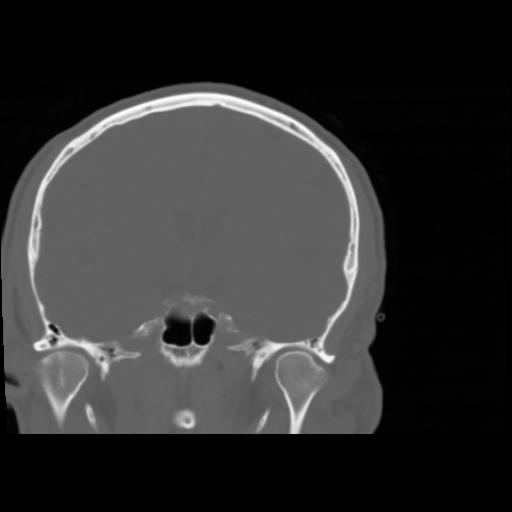

5 CEREBRO,,Coronal,3.000,CEREBRO,Coronal,